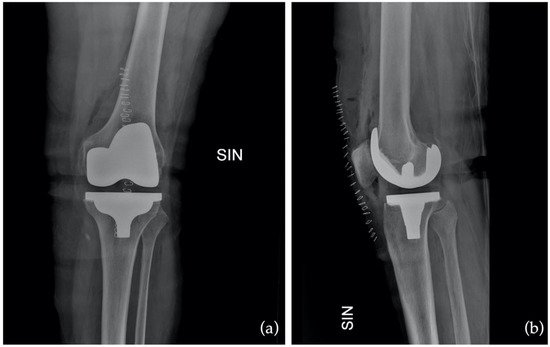

Aligning the prosthetic components to match your natural knee

Your knee replacement involves inserting a set of prosthetic components — typically made from a combination of metal alloys and medical-grade plastic — to recreate the surfaces of the joint. These components are positioned to match the natural alignment and movement of your original knee, as closely as possible. In many cases, Prof. Hunt or Prof. Sallen may use computer-assisted techniques or patient-specific guides to help with positioning the implants with a high degree of precision. This helps restore natural joint kinematics and may contribute to improved function, better joint stability, and reduced wear over time.